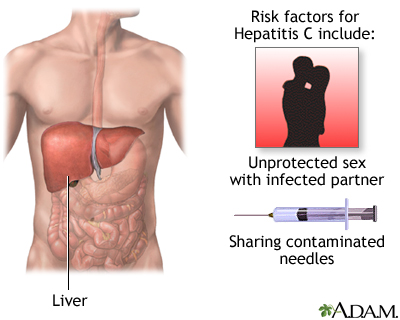

Chronic Viral Hepatitis

Chronic viral hepatitis, both hepatitis B and hepatitis C, is another major cause of cirrhosis. Chronic hepatitis C is a more common cause of cirrhosis in developed countries, while hepatitis B is a more common cause of cirrhosis worldwide, especially in sub-Saharan Africa and parts of Asia. People with chronic hepatitis B who are co-infected with hepatitis D are especially at risk for cirrhosis. The longer a person has chronic hepatitis, the greater the risk for eventually developing cirrhosis.

Hepatitis viruses produce inflammation in liver cells, causing injury or destruction. If the condition is severe and long-term, the cell damage becomes progressive, leading to severe scarring of the liver.

Hepatitis C is caused by a virus that causes inflammation in the liver, which may lead to cirrhosis. Consumption of alcohol enhances the damage done to the liver by the hepatitis C virus. The people at greatest risk of contracting and spreading hepatitis C are those who share needles for injecting drugs. People who have sex with multiple partners are also at increased risk of contracting hepatitis C. People who receive blood transfusions contaminated with hepatitis C virus are at great risk of developing active hepatitis.